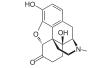

In the 19th century, two major scientific advances were made that had far-reaching effects. Around 1804, German pharmacist Friedrich Sertürner isolated morphine from opium. He described its crystallization, structure, and pharmacological properties in a well-received paper in 1817.[211][213][208][214] Morphine was the first alkaloid to be isolated from any medicinal plant, the beginning of modern scientific drug discovery.[211][215]

Several semi-synthetic opioids were developed in Germany in the 1910s. The first, oxymorphone, was synthesized from thebaine, an opioid alkaloid in opium poppies, in 1914.[228] Next, Martin Freund and Edmund Speyer developed oxycodone, also from thebaine, at the University of Frankfurt in 1916.[229] In 1920, hydrocodone was prepared by Carl Mannich and Helene Löwenheim, deriving it from codeine. In 1924, hydromorphone was synthesized by adding hydrogen to morphine. Etorphine was synthesized in 1960, from the oripavine in opium poppy straw. Buprenorphine was discovered in 1972.[228]

- Natural opiates: alkaloids contained in the resin of the opium poppy, primarily morphine, codeine, and thebaine, but not papaverine and noscapine which have a different mechanism of action

Opium alkaloids and derivatives

Phenanthrenes naturally occurring in (opium):